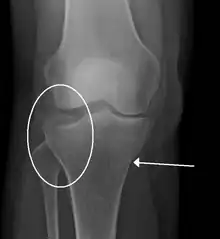

| A severe tibial plateau fracture with an associated fibular head fracture | |

Fractures of the tibial plateau are caused by a varus (inwardly angulating) or valgus (outwardly angulating) force combined with axial loading or weight bearing on knee. The classically described situation in which this occurs is from a car striking a pedestrian's fixed knee (bumper fracture). A bumper fracture is usually a fracture of the lateral tibial plateau, caused by a forced valgus movement. This causes the lateral part of the distal femur and the lateral tibial plateau to come into contact, compressing the tibial plateau and causing the tibia to fracture. The name of the injury is because it was described as being caused by the impact of a car bumper on the lateral side of the knee while the foot is planted on the ground, although this mechanism is only seen in about 25% of tibial plateau fractures.[5] The term "bumper fracture" was coined in 1929 by Cotton and Berg.[6] Fracture of the neck of the fibula may also be found, and associated injury to the medial collateral ligament or cruciate ligaments occurs in about 10% of cases.[7][8]